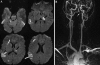

This pictorial review is based on our experience of the follow-up of 120 patients at our multidisciplinary center for hereditary hemorrhagic telangiectasia (HHT). Rendu-Osler-Weber disease or HHT is a multiorgan autosomal dominant disorder with high penetrance, characterized by epistaxis, mucocutaneous telangiectasis, and visceral arteriovenous malformations (AVMs). The research on gene mutations is fundamental and family screening by clinical examination, chest X-ray, research of pulmonary shunting, and abdominal color Doppler sonography is absolutely necessary. The angioarchitecture of pulmonary AVMs can be studied by unenhanced multidetector computed tomography; however, all other explorations of liver, digestive bowels, or brain require administration of contrast media. Magnetic resonance angiography is helpful for central nervous system screening, in particular for the spinal cord, but also for pulmonary, hepatic, and pelvic AVMs. Knowledge of the multiorgan involvement of HHT, mechanism of complications, and radiologic findings is fundamental for the correct management of these patients.